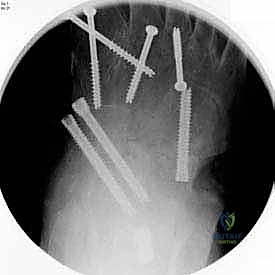

بعد التأكد من الوضعية المثالية للعظام، يتم تثبيتها بقوة باستخدام مسامير معدنية مجوفة من التيتانيوم (Cannulated Screws) أو شرائح معدنية خاصة. يتم إدخال المسامير تحت توجيه الأشعة السينية المباشرة (Fluoroscopy) داخل غرفة العمليات لضمان الدقة المتناهية. هذه المسامير تضغط العظام معاً وتمنع أي حركة حتى يحدث الالتئام التام.

يتم إغلاق الأنسجة والجلد بخيوط تجميلية دقيقة لتقليل الندبات، ثم توضع القدم في جبيرة خلفية مبطنة جيداً لحمايتها من أي حركة وتقليل التورم.